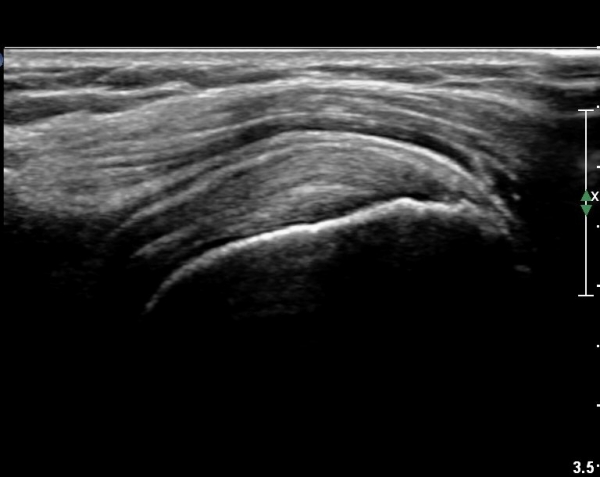

°ß°©ÇÏ±Ù°Ç Á¾´Ü¸é°Ë»ç¿¡¼­ ¼Ò°áÀý Ç¥ÃþÀÇ ºÒ±ÔÄ¢º¯È­(bone irregularity)¿Í °Ç ½ÇÁú³»

¼±»óÀÇ Àú¿¡ÄÚ À½¿°ÀÌ °üÂûµÈ´Ù(»çÁø 5).